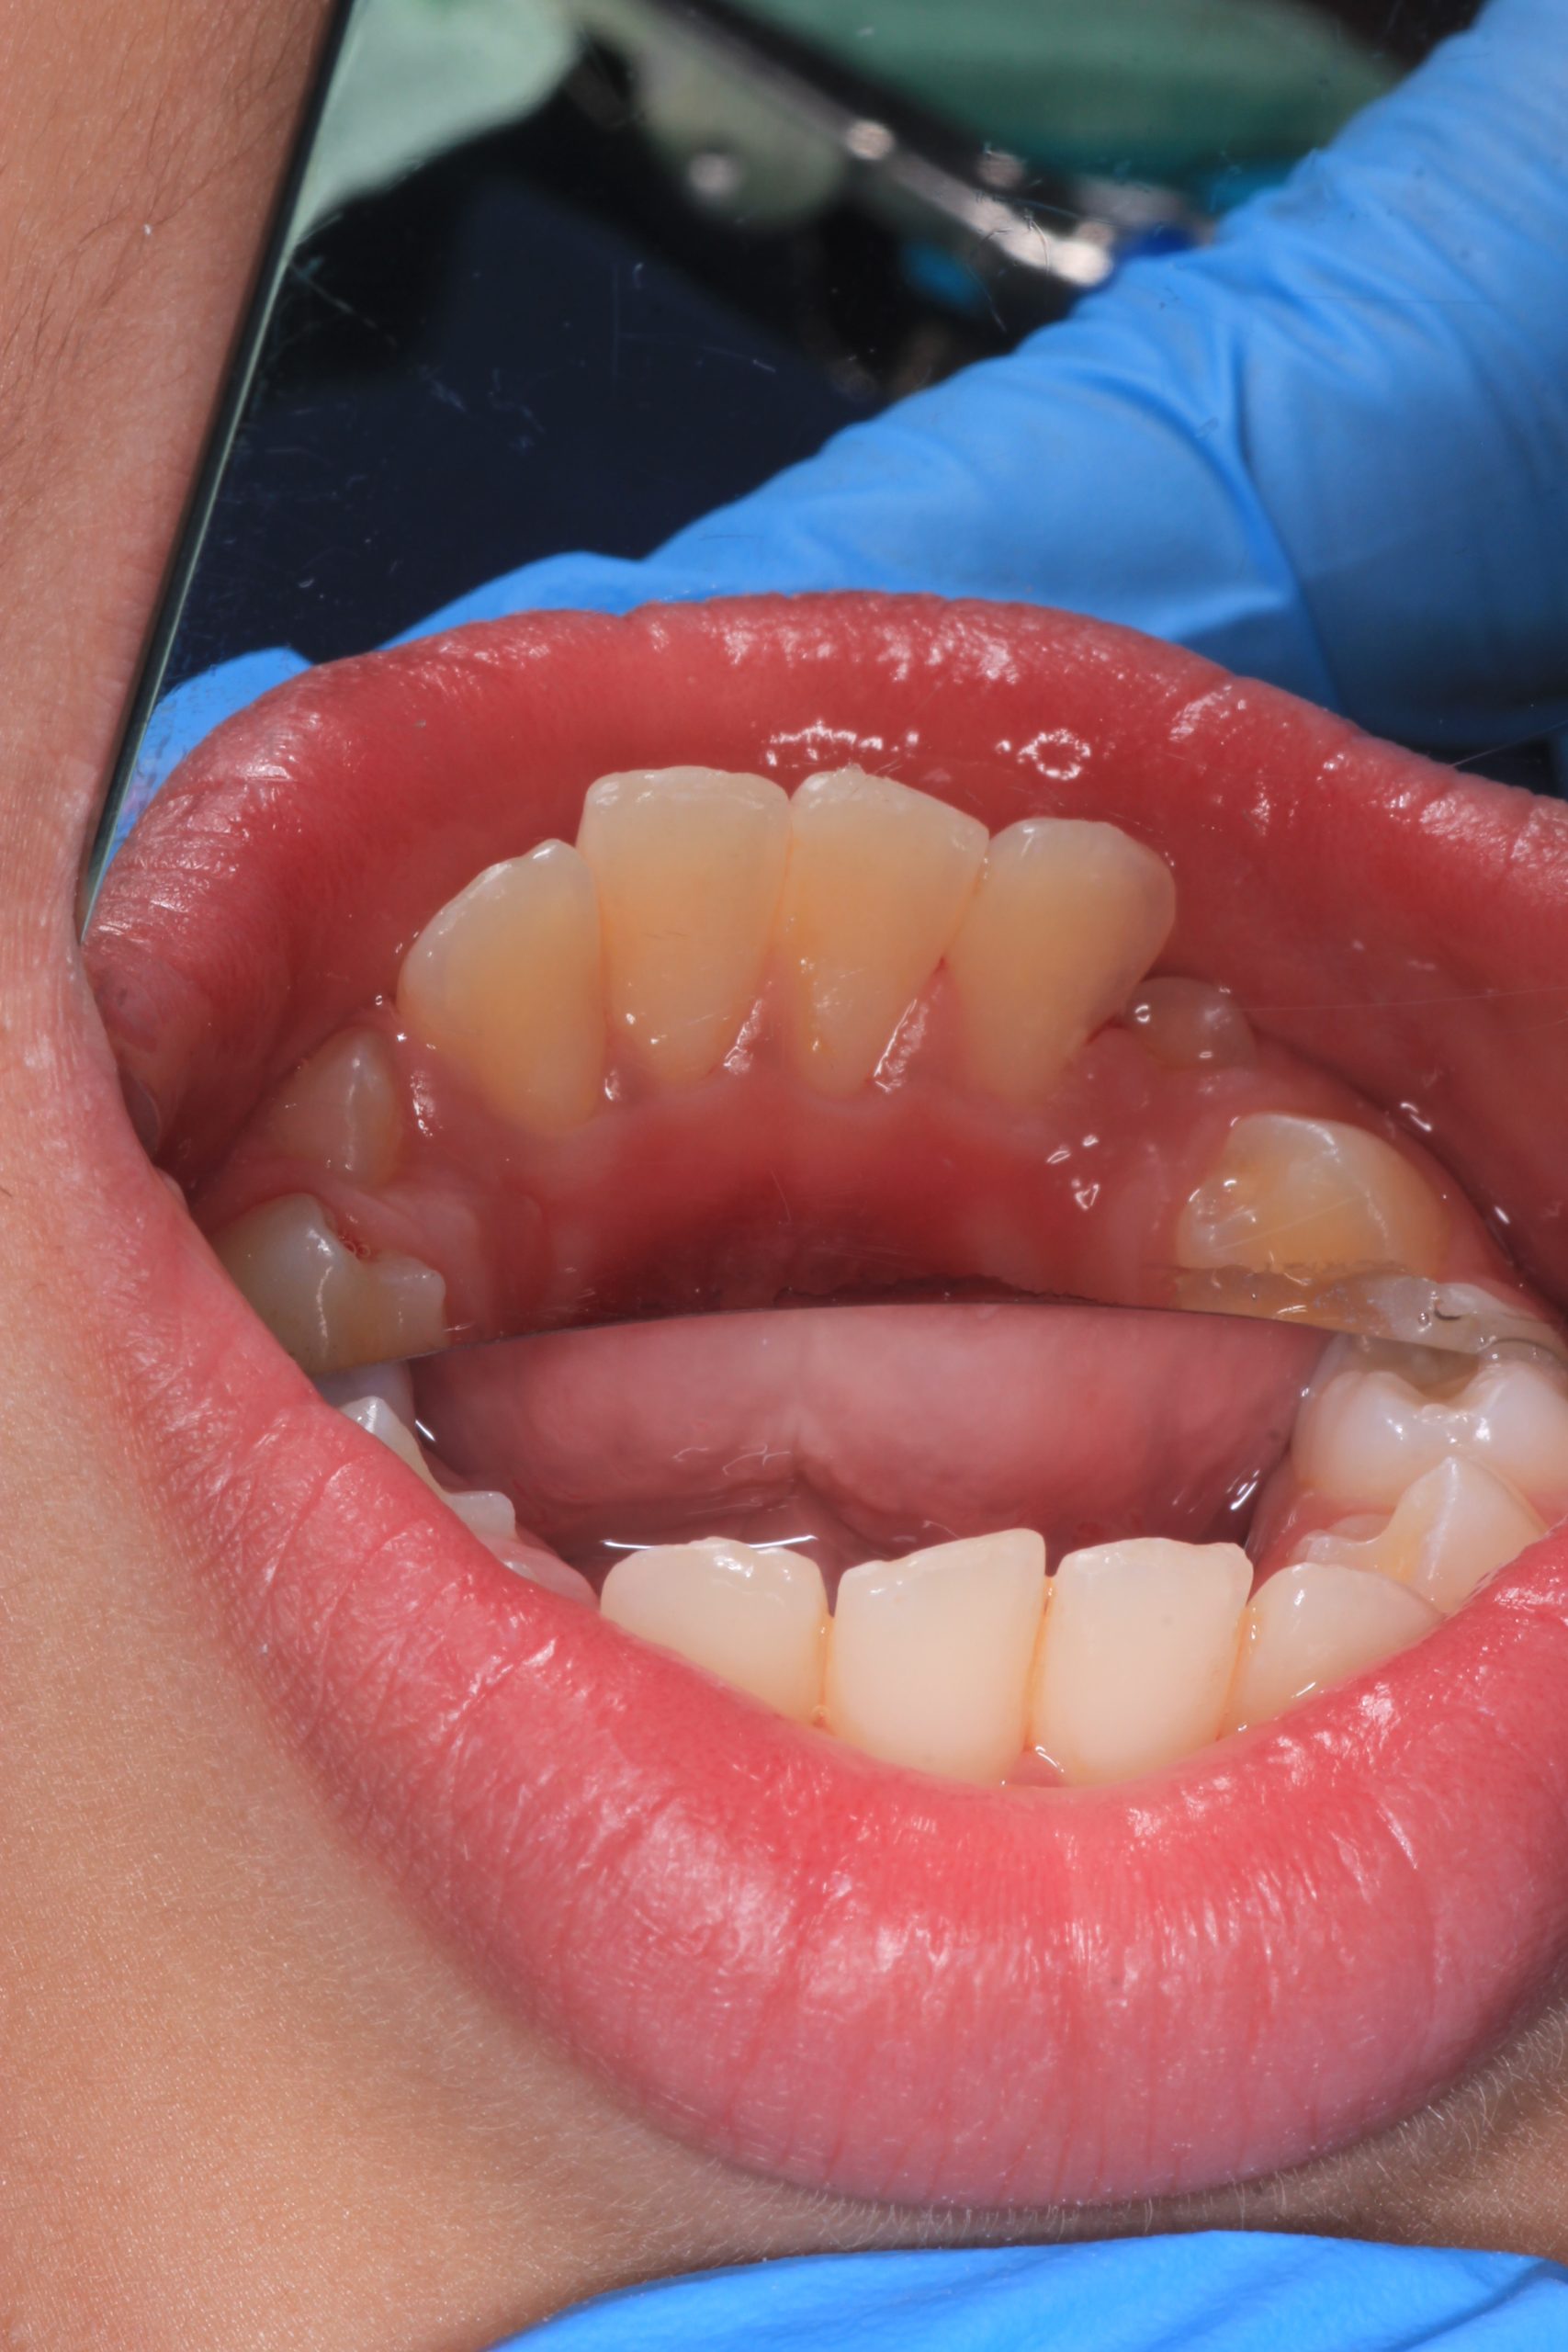

We examine the condition of teeth, gums, and bite. - Plaque Disclosure with Special Indicators

Areas that weren’t cleaned well appear purple. The darker the shade, the older the plaque. This helps both kids and parents understand where brushing needs to improve. - Brushing Training & Home Care Tools Selection